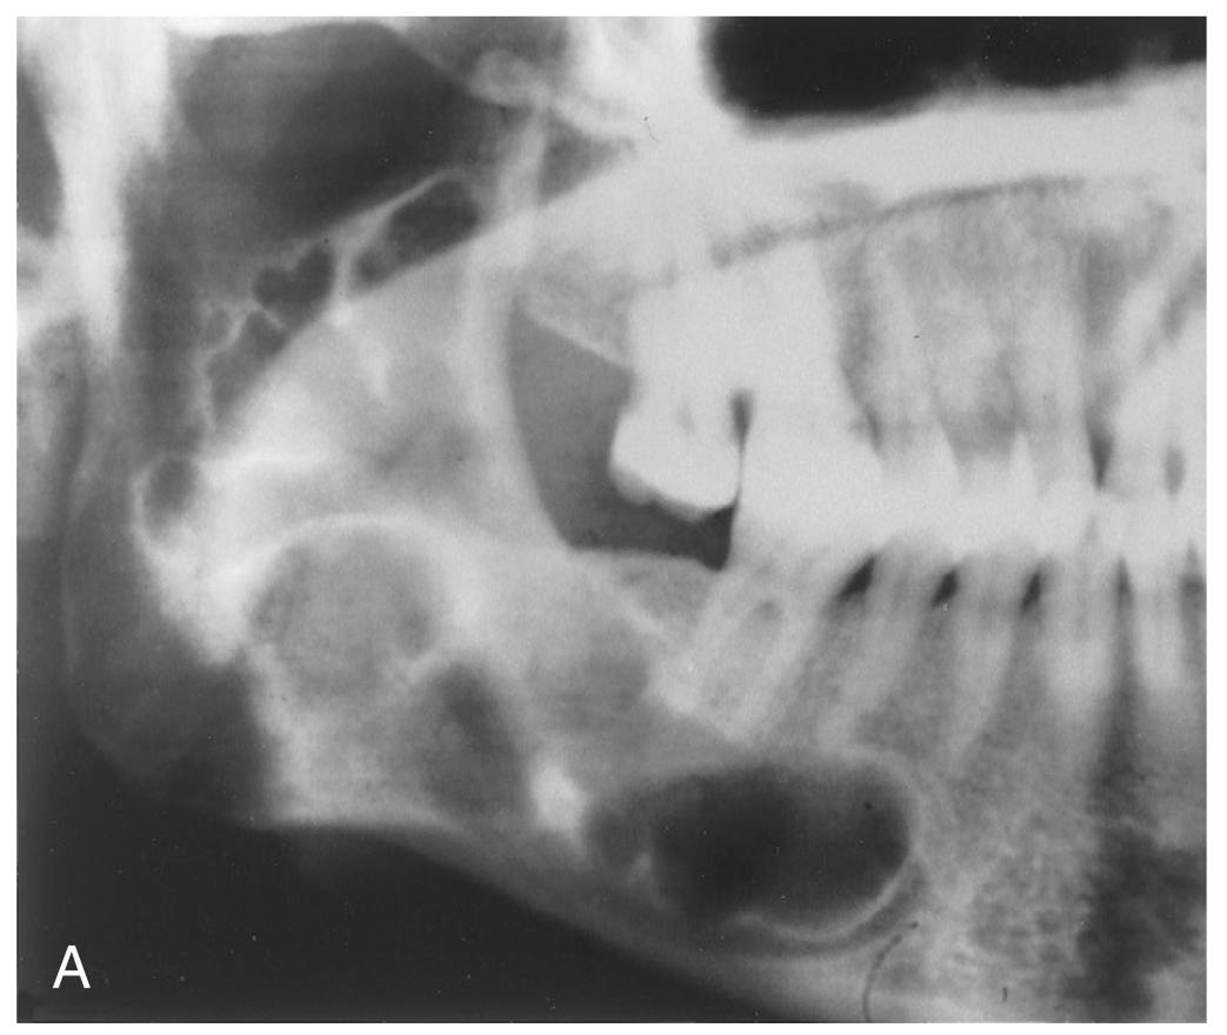

4. This 72-year-old woman presented with loose 20-yearold dentures and slight intermittent pain under the lower denture. She stated she had her teeth extracted because of severe untreated caries and abscessed teeth. The radiolucent lesion was detected on a radiograph of the painful area.

What is your diagnostic impression?